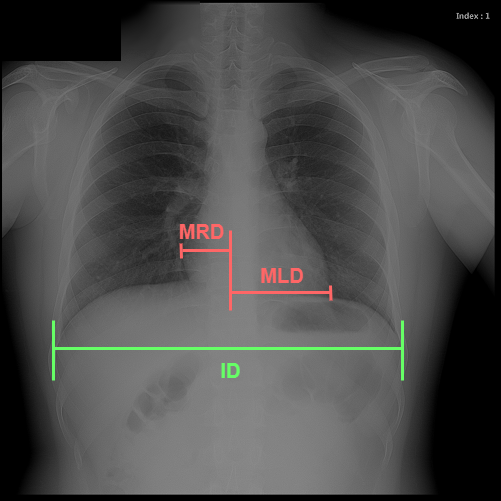

Chest radiography is the most common tool for detecting cardiomegaly due to the low cost and high availability of devices to obtain chest X-ray images. From chest X-ray images, radiologists employ CTR as one of the most important indicators of cardiomegaly due to the simplicity of the calculation. CTR of a chest X-ray image is calculated as cardiac diameter (the diameter of the heart) divided by the thoracic diameter (the diameter of the chest). Specifically, CTR can be calculated from three measurements, , the midline-to-right heart diameter, , the midline-to-left heart diameter, and , the internal diameter of chest [2, 3], as

| (1) |

where and is measured from the greatest perpendicular diameter from midline to right and left heart border, respectively. Figure 1 visualizes the details of CTR calculation. A CTR value of is generally considered to indicate the upper limit of normal.